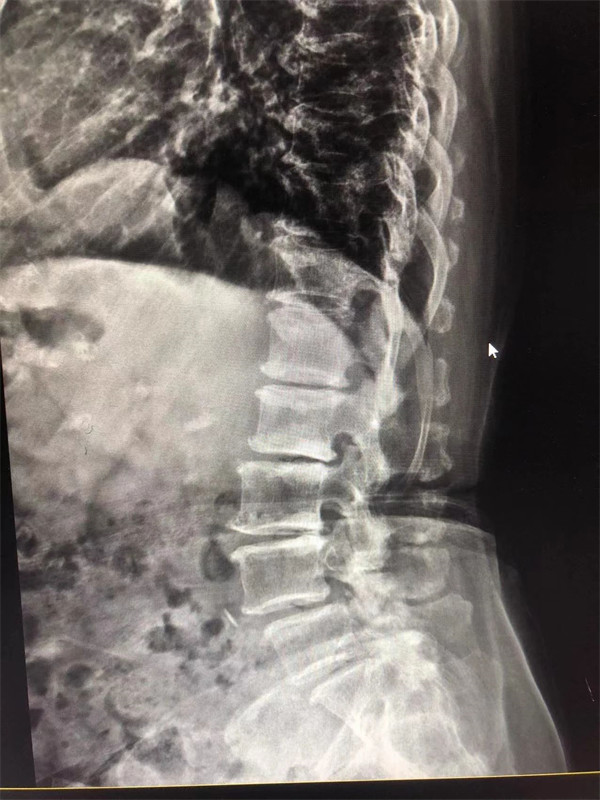

戈主任仔細(xì)詢問(wèn)阿婆病情癥狀,綜合查體及MRI片情況,認(rèn)為阿婆有明顯的腰椎滑脫,腰椎管狹窄,這是引發(fā)阿婆病痛的主要因素。

手術(shù)前↓